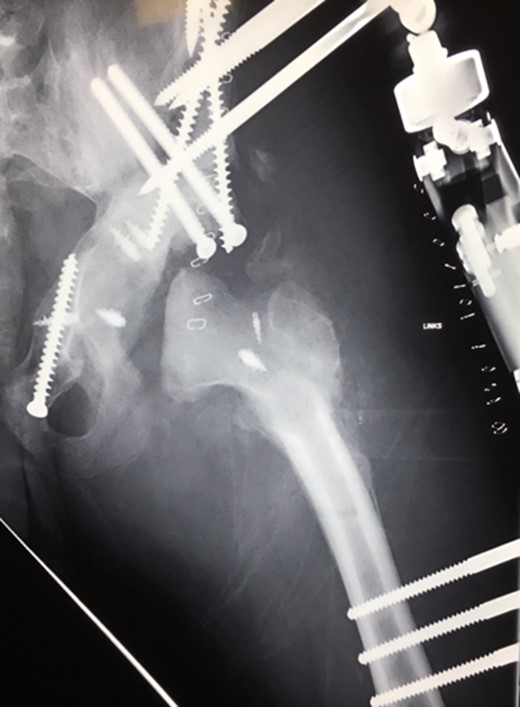

(A + B): (2019) (A) x ray of the pelvis after a 10 year follow up. The right head further migrated und subluxated and femoral head necrosis is visible, new bone formation at the ileum stabilizing the joint. At the left side high dislocation of the hip with fully necrosis of the head and ankylosis of the hip joint. (B) MRI showing hip effusion around the joint which is painless.

At this stage patient’s walking ability was already limited due to muscle weakness and rubbing in the hip joints, so we recommended no further walking and weight bearing. Further follow-up at 5 years (Fig. 7) and 10 years (Fig. 8A) until today showed radiologically complete absorption of the left femoral head and the right hip continuously moving cranially creating a false acetabulum and a flattened femoral head. At final follow up the patient was in a wheel chair but able to bend both hips up to 110 degrees without noticeable pain, he could stand up with help for a short time and showed a massive Charcot joint with effusion (Fig. 8B) of the right hip without further clinical implications.